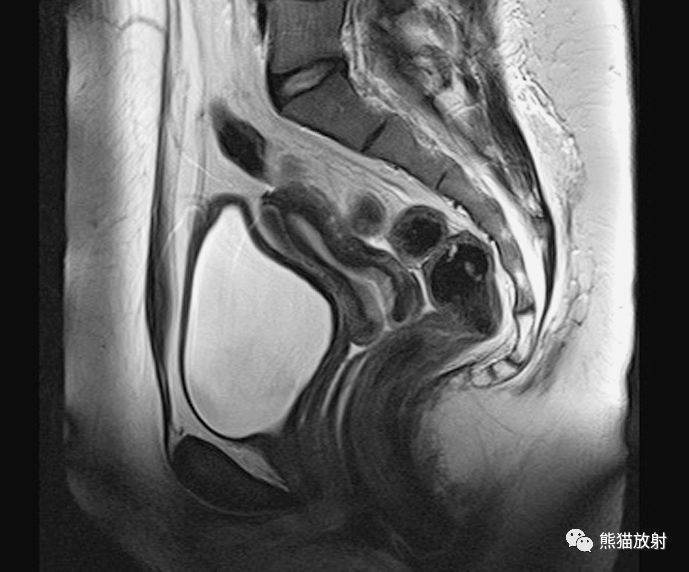

MR断层解剖

矢状T2WI

1、子宫体(肌层),2、子宫(结合带),3、子宫(内膜),4、子宫(宫腔),5、腹直肌,6、膀胱子宫陷凹,7、膀胱,8、脂肪层(膀胱、尿道与阴道之间),9、阴道,10、尿道,11、耻骨,12、会阴深横肌,13、耻骨弓状韧带,14、大/小阴唇,15、宫颈皱褶,16、直肠,17、宫颈管,18、直肠子宫陷凹(Douglas陷凹),19、宫颈口,20、肛尾韧带及提肛肌,21、脂肪层(阴道与直肠之间),22、肛管及肛门,23、会阴体,24、肛门外括约肌。